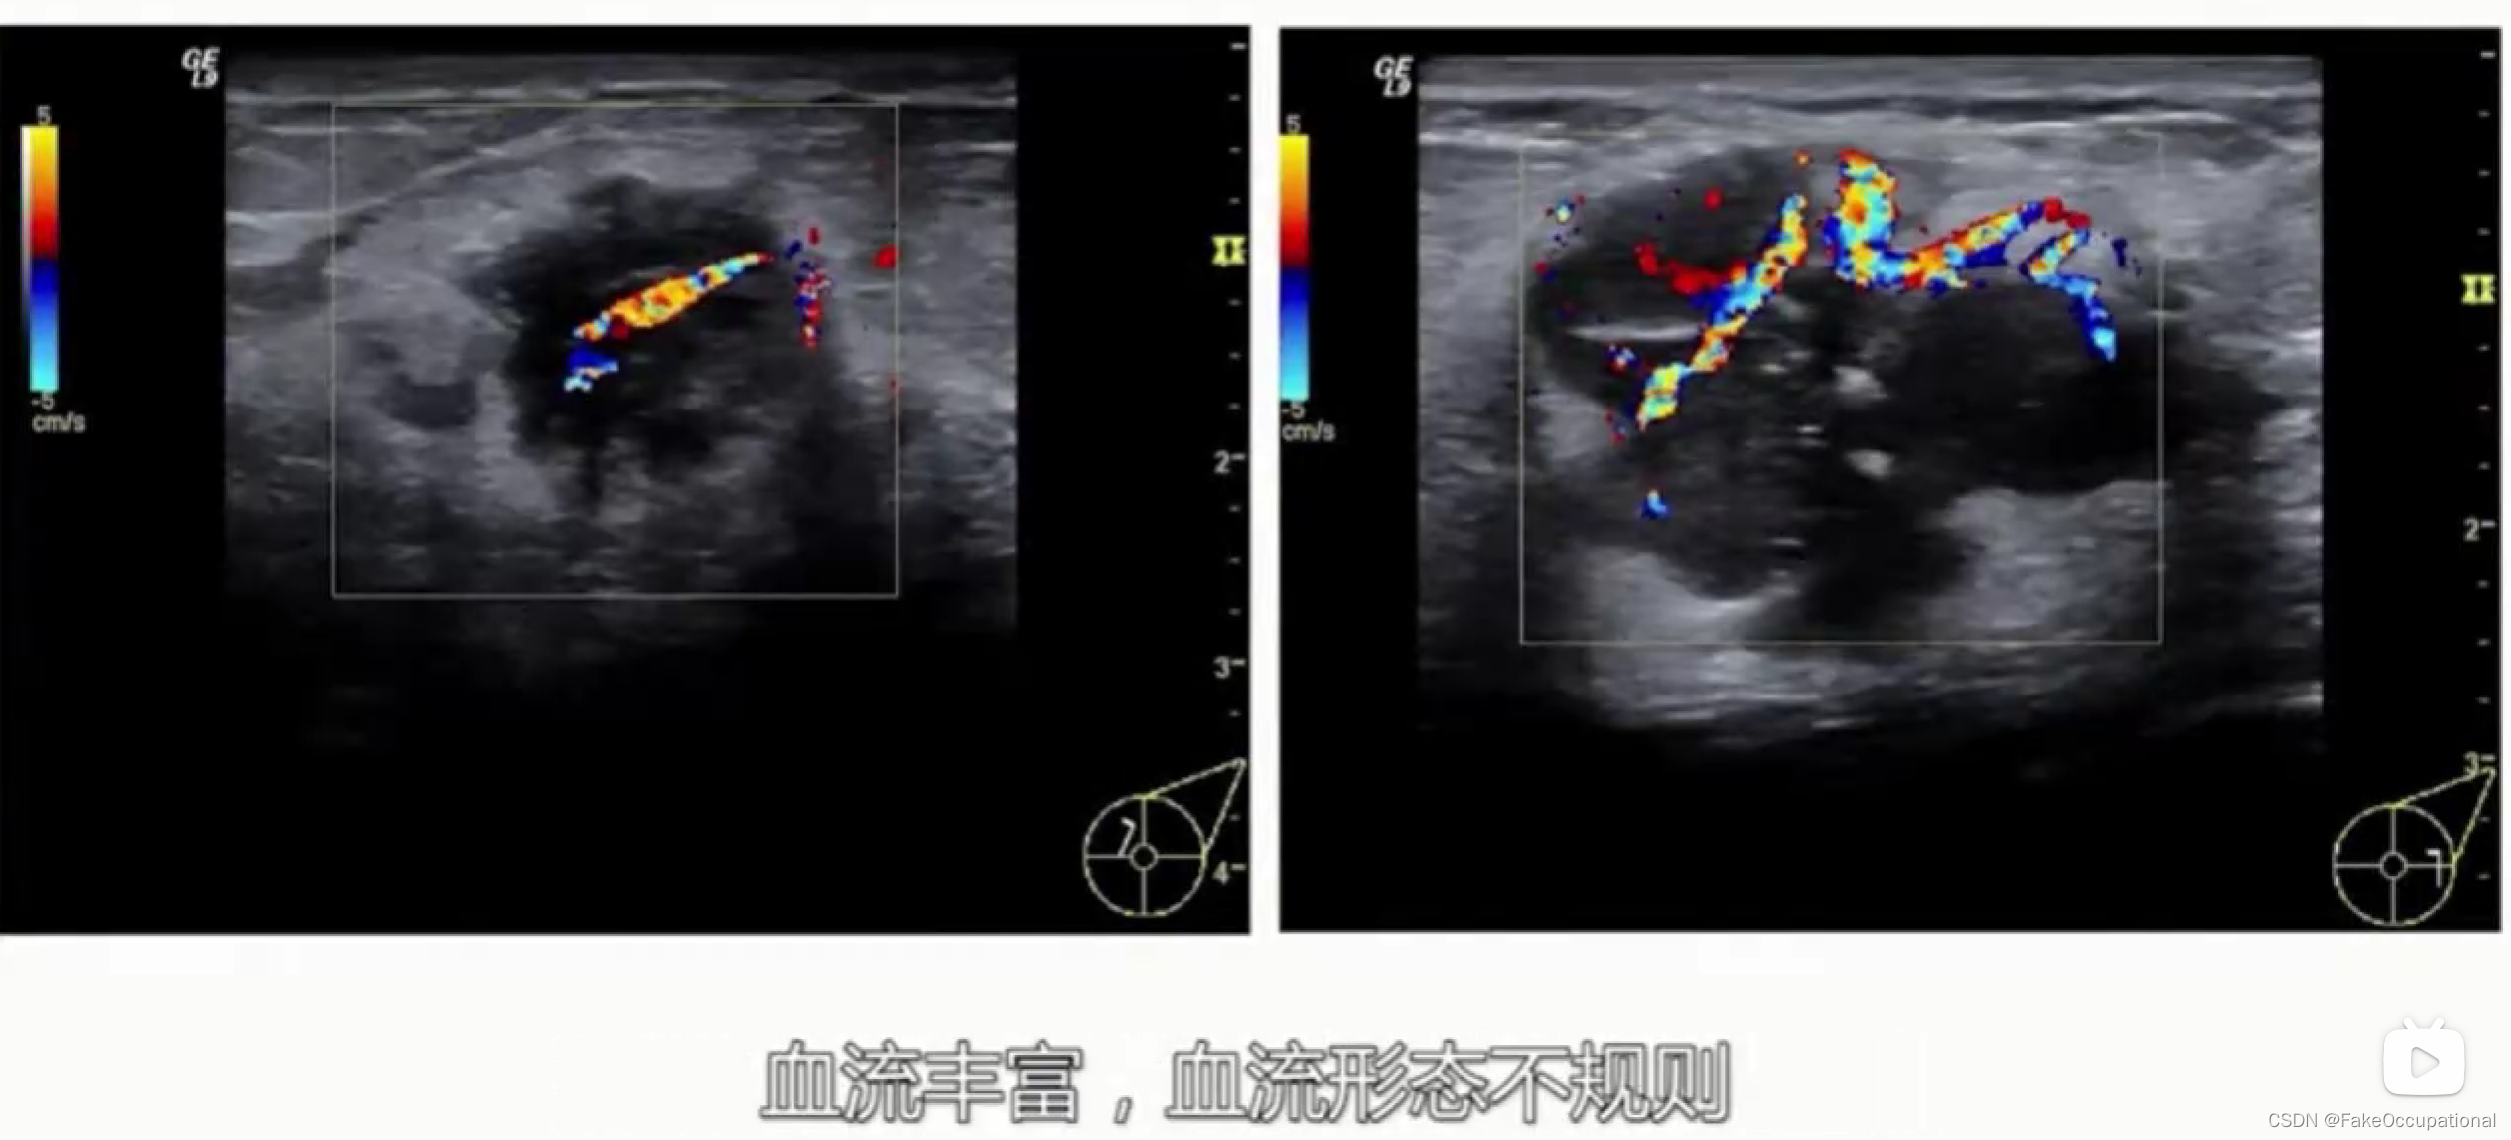

- 彩色编码实时显示血流方向、速度及血流性质:彩色多普勒血流成像(CDFI),彩色多普勒能量图(CDE)

乳腺癌

- 患者18岁,微小癌

- 其理论依据是恶性肿瘤常星离心性生长

- 淋巴结转移

乳腺超声进展

- 前者以彩色编码不同组织的弹性大小,